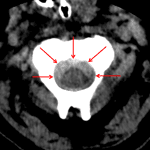

- Offset of the lateral masses of C1 with respect to the occipital condyles consistent with atlanto-occipital subluxation

- Hyperattenuating material in the anterior aspect of the spinal canal at the foramen magnum extending inferiorly to the level of C2-C3 without significant mass effect on the cord

- Bilateral atlanto-occipital subluxation (extensive ligamentous injury subsequently confirmed on MRI)

- Epidural hematoma

Offset of the lateral masses of C1 with respect to the occipital condyles concerning for ligamentous injury. Recommend MRI for further evaluation.

Hyperattenuating material in the anterior aspect of the spinal canal at the foramen magnum extending inferiorly to the level of C2-C3 likely represents an epidural hematoma. No significant mass effect on the cord.